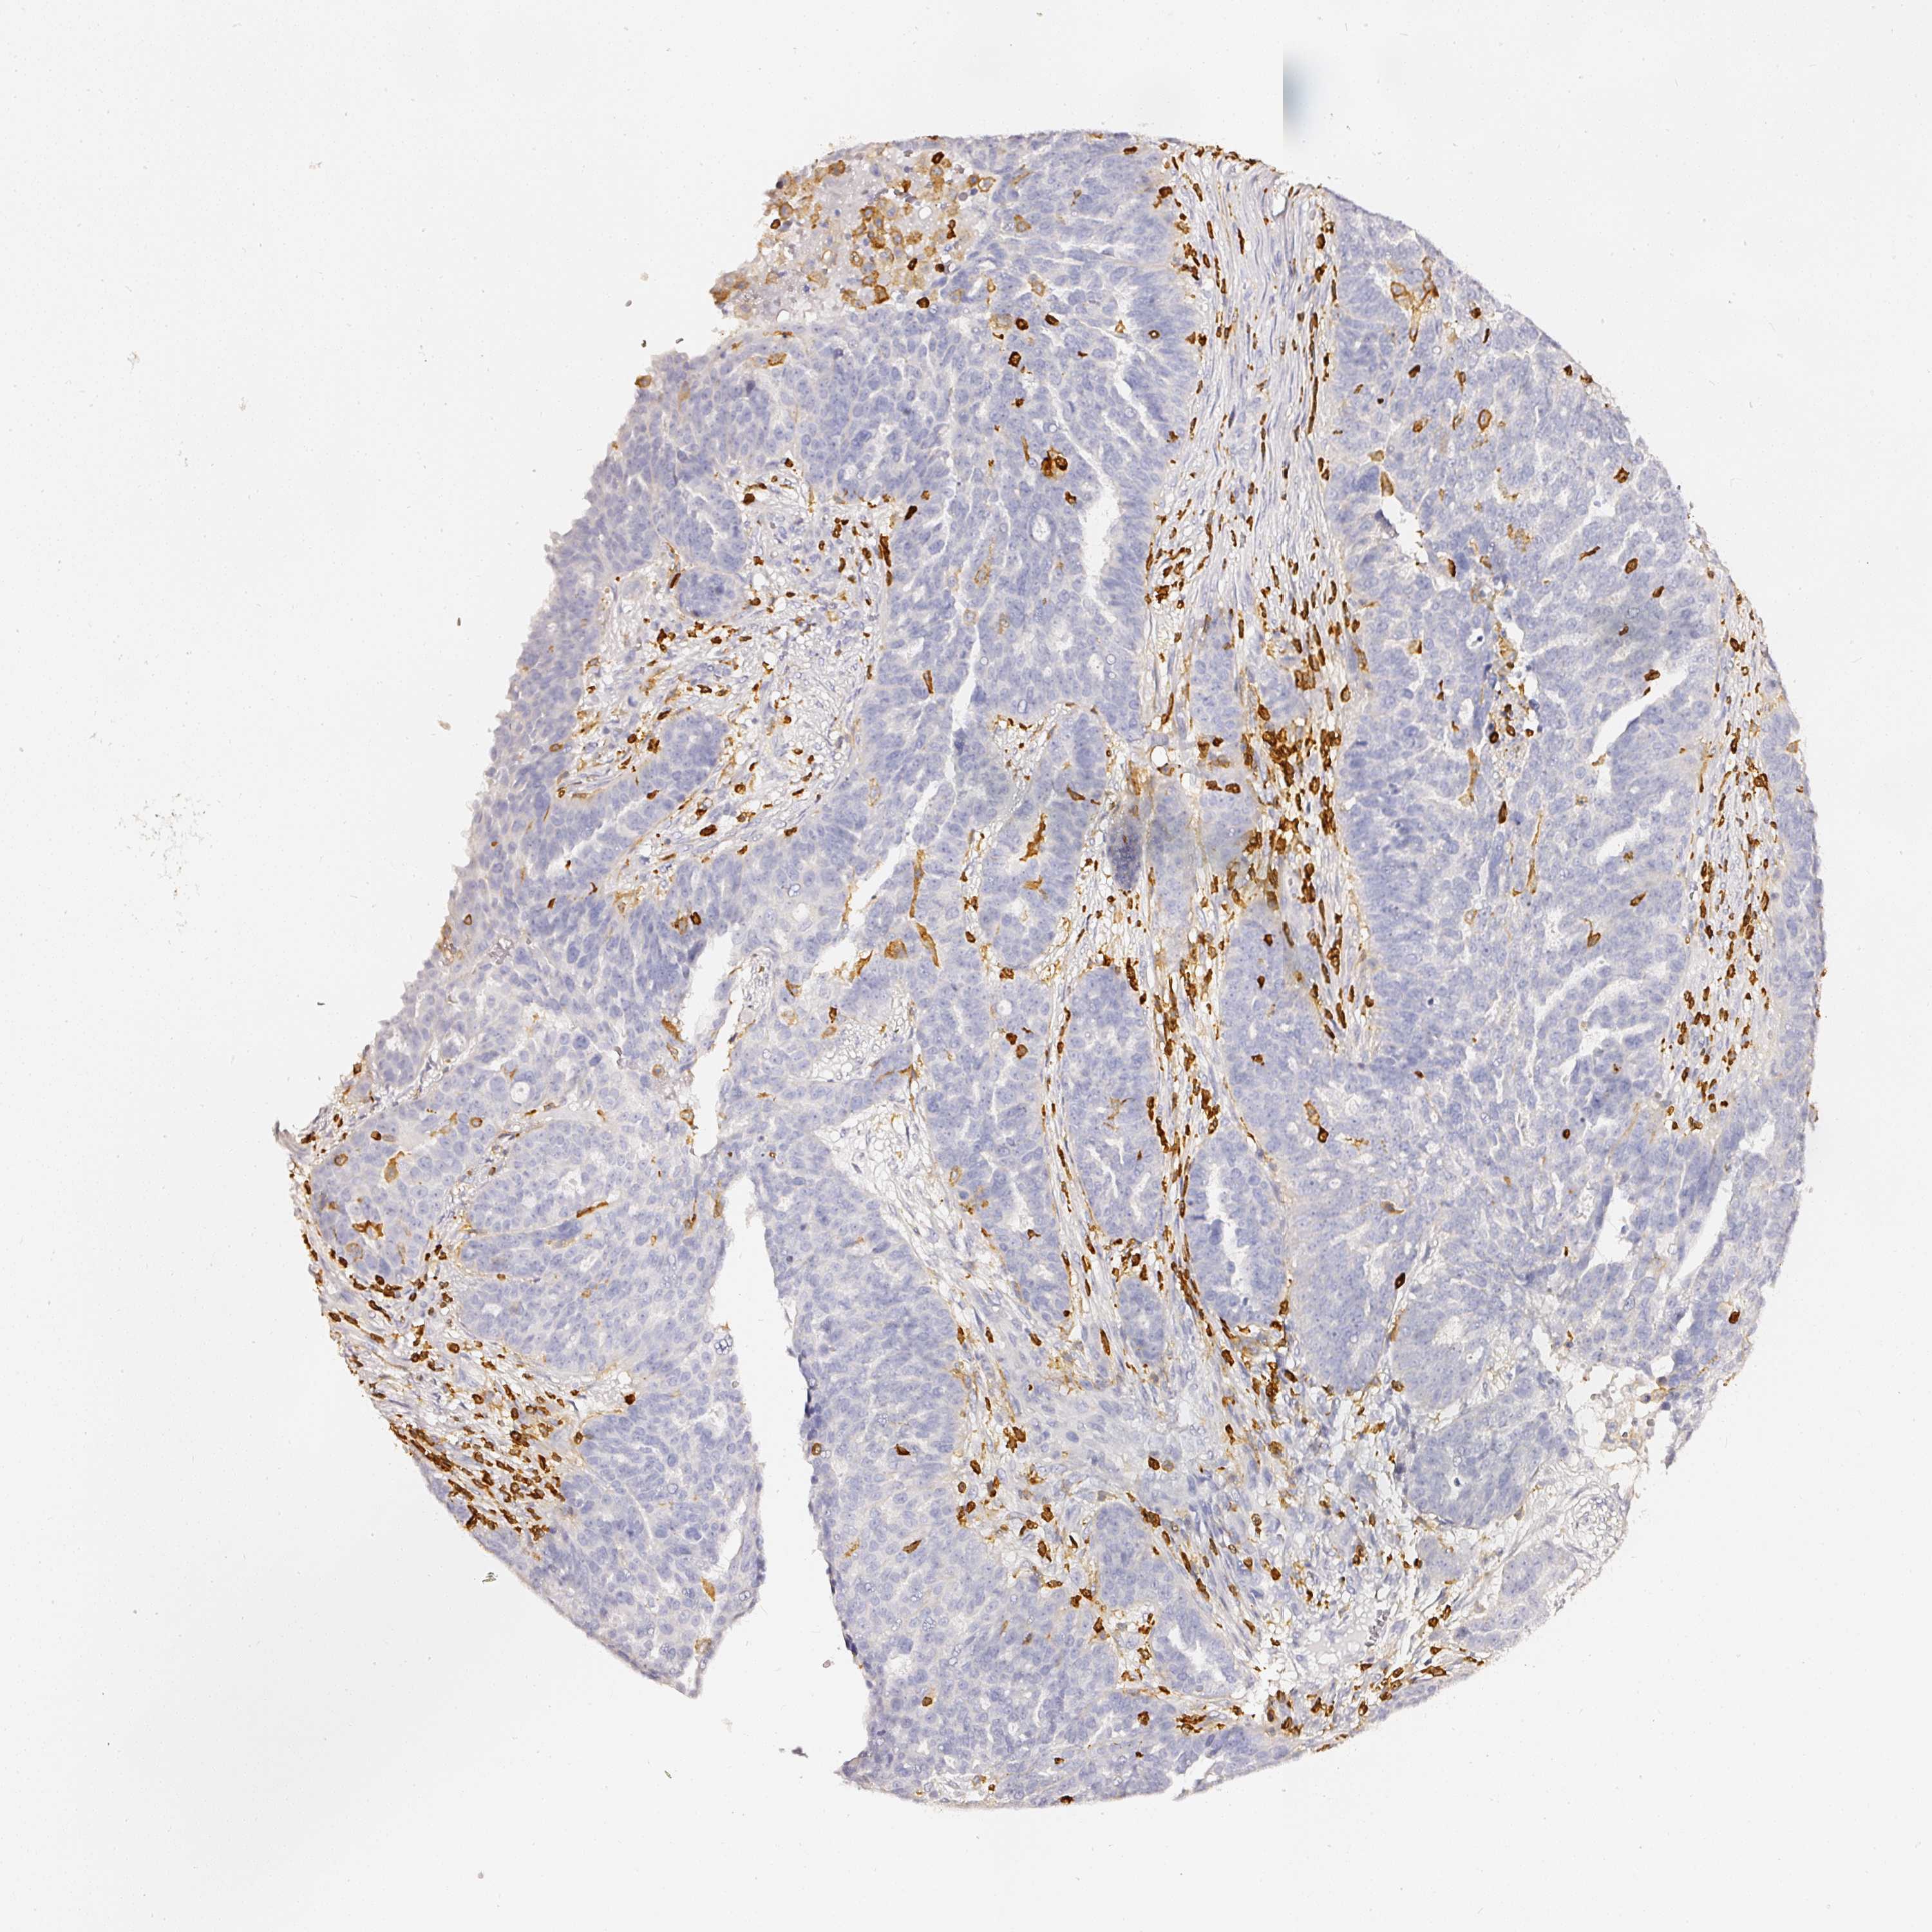

OVARIAN CANCER - Protein expressioni

A mouse-over function shows sample information and annotation data. Click on an image to view it in a full screen mode. Samples can be filtered based on level of antibody staining by selecting one or several of the following categories: high, medium, low and not detected. The assay and annotation is described here.

Note that samples used for immunohistochemistry by the Human Protein Atlas do not correspond to samples in the TCGA dataset.

Antibody stainingi

Antibody staining in the annotated cell types in the current human tissue is reported as not detected, low, medium, or high, based on conventional immunohistochemistry profiling in selected tissues. This score is based on the combination of the staining intensity and fraction of stained cells.

Each image is clickable and will lead to virtual microscopy that enables deeper exploration of all samples and also displays staining intensity scores, fraction scores and subcellular localization as well as patient and tissue information for each sample.

Antibody HPA018849

Antibody HPA019536

Antibody CAB033987

Cystadenocarcinoma, serous, NOS

Carcinoma, endometroid

Cystadenocarcinoma, mucinous, NOS

Carcinoma, NOS